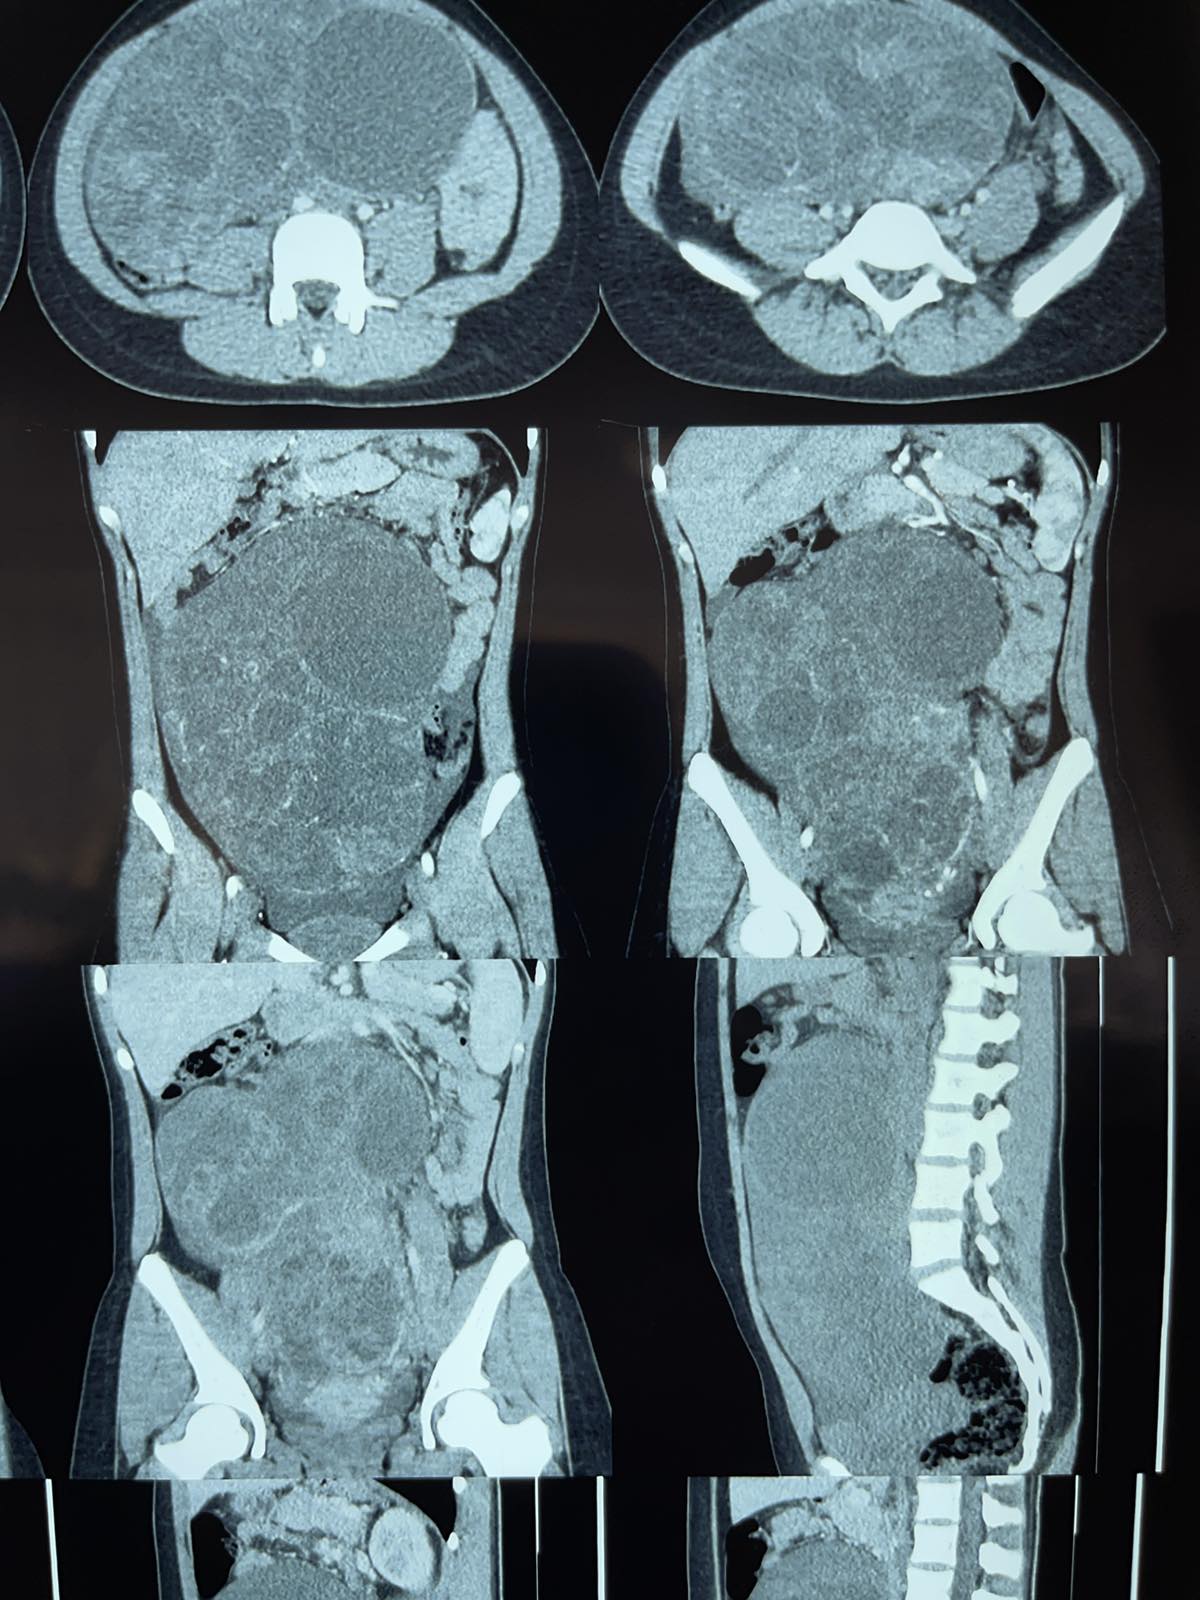

Pacienta, o adolescentă de 15 ani, a fost internată în instituția noastră cu un istoric de 12 luni de dureri abdominale periodice, mărire a volumului abdominal și amenoree La spitalizare, examenul ecografic abdominal a evidențiat o formațiune abdominală majoră. Datele imagistice CT cu contrast intravenos au permis vizualizarea în compartimentul anterior al bazinului mic, intraperitoneal cu extensie craniană în proiecția mezogastrului și a flancurilor bilaterale a unei formațiuni chistice masive, poliseptate, polilobate, cu dimensiunile de 24,0cm x 20,0cm x 10,6cm. Formațiunea, care avea o structură neomogenă cu contur bine definit, prezenta un conținut mixt fluido-chistic, asociat cu prezența mai multor vase intrastromale, fără mărire patologică postcontrast, efect de masă pronunțat exercitat prin compresie și luxație a organele abdominale și pelvine, compresia vezicii urinare, bombarea peretelui abdominal anterior. Semne de acumulare moderată de lichid liber în spațiul intraperitoneal (cu densitate +12UH). Ovarele și trompele uterine nu au fost cu siguranță determinate.